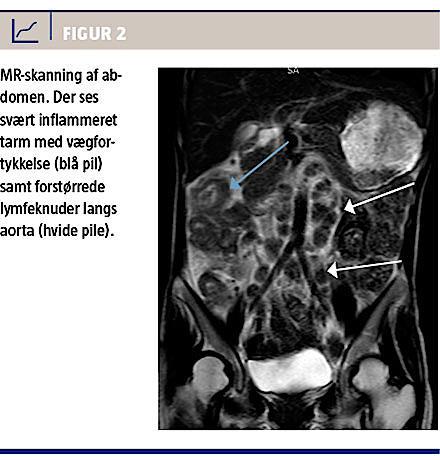

Koloskopien viste nekrotiske områder med cobblestone-tegning i transversum frem til højre fleksur, hvor man ikke kunne komme videre frem pga. forandringerne (Figur 1). En MR-skanning viste flere steder fortykkelse af tarmvæggen, betydeligt ødem ileocøkalt og forstørrede glandler paraaortalt og langs iliacakarrene (Figur 2).

We describe a case of intestinal tuberculosis in a 34-year-old Indonesian woman. She presented with diarrhoea, weight loss, fever and night sweat over a period of weeks. She underwent colonoscopy which showed a major cobblestone pattern like necrosis in part of the colon. An MR scan showed oedema involving the small intestine near the ileocoecal area and abdominal lymphadenopathy. Because of the patient history of recent TB exposure, ethnicity and positive T-SPOT-TB, she was given a course of four-drug tuberculosis treatment and responded quickly. Later on Mycobacterium tuberculosis was found in faeces culture.